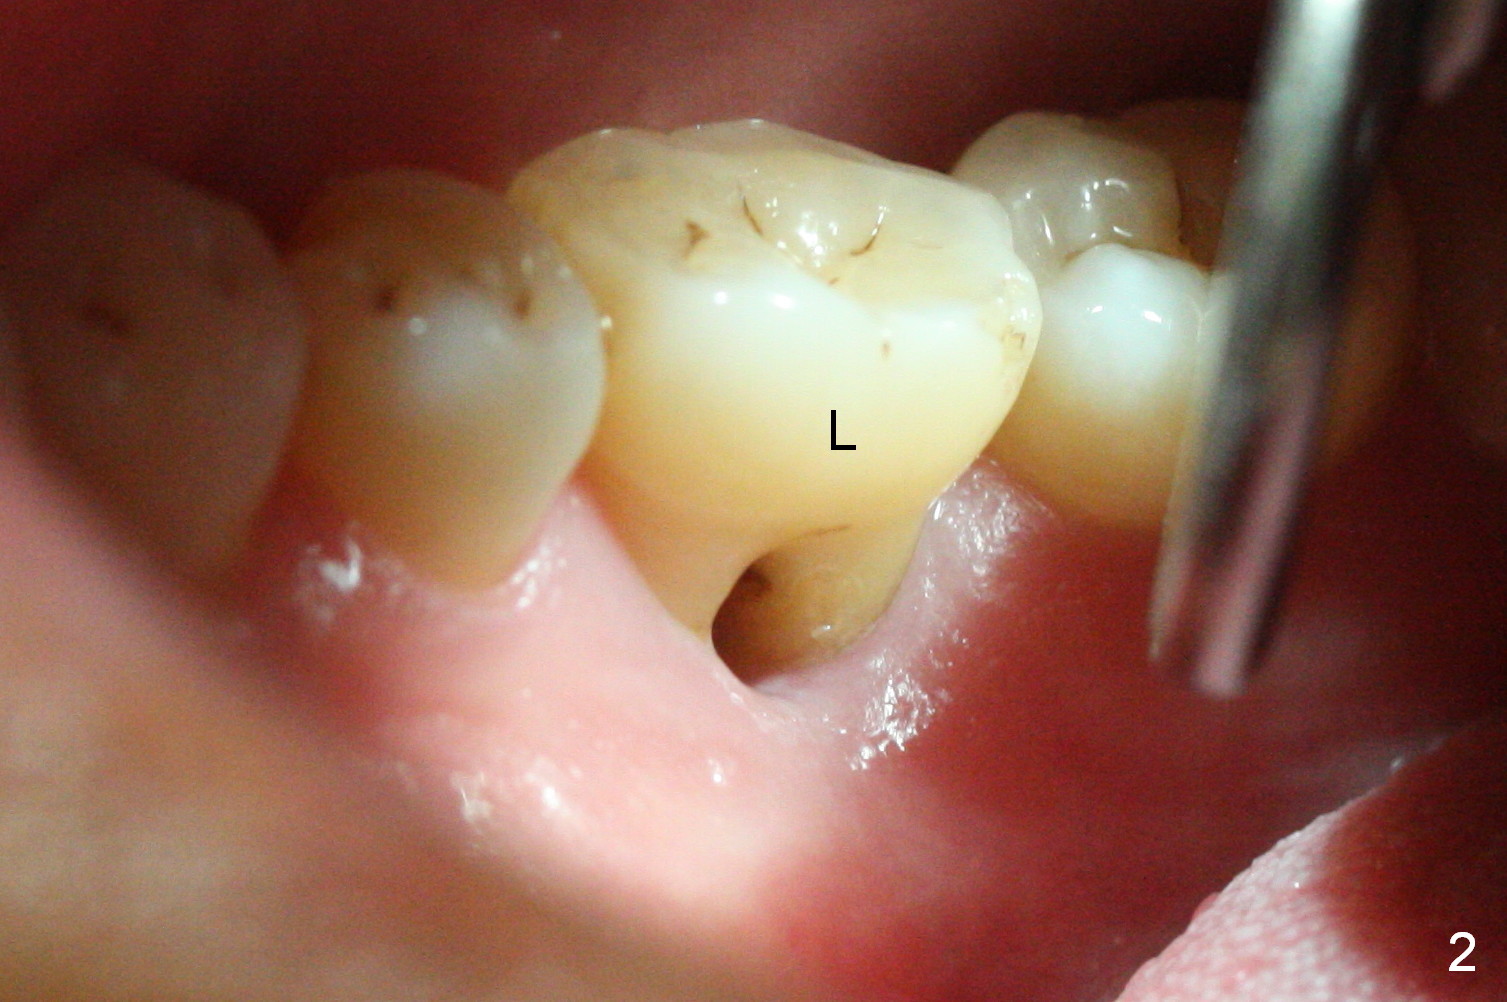

After extraction of the tooth #30 with Class V furcation involvement (Fig.1 (>),2 (L: lingual)), initial osteotomy depth is 8 mm with infiltration anesthesia, but a parallel pin is able to be inserted for 16 mm without pain (Fig.3). There is oozing from the osteotomy. Osteotomy increases in diameter with depth at 8 mm (Fig.4 (3.8 mm drill),5 (5.3 mm tap)). As the Inferior Alveolar Canal (IAC) is indistinct with increased pain during osteotomy, a 5.9x6 mm implant is placed with >50 Ncm following Septocaine infiltration (Fig.6). When bone graft (Fig.7 *) and 7.8x5.5(6) mm abutment (Fig.7,8) are placed, panoramic X-ray is taken (Fig.9). There appears to be a thick layer of spongy bone in the posterior mandible between the red and yellow dashed lines (Fig.5,9). Panoramic X-ray and/or CBCT should be taken if preop PA does not reveal IAC. This patient seems to be a bruxer. There are mandibular tori. Bone loss (furcation involvement) is not proportional to his oral hygiene status. Functional loading (progressive) should be delayed due to bruxism and the short implant.